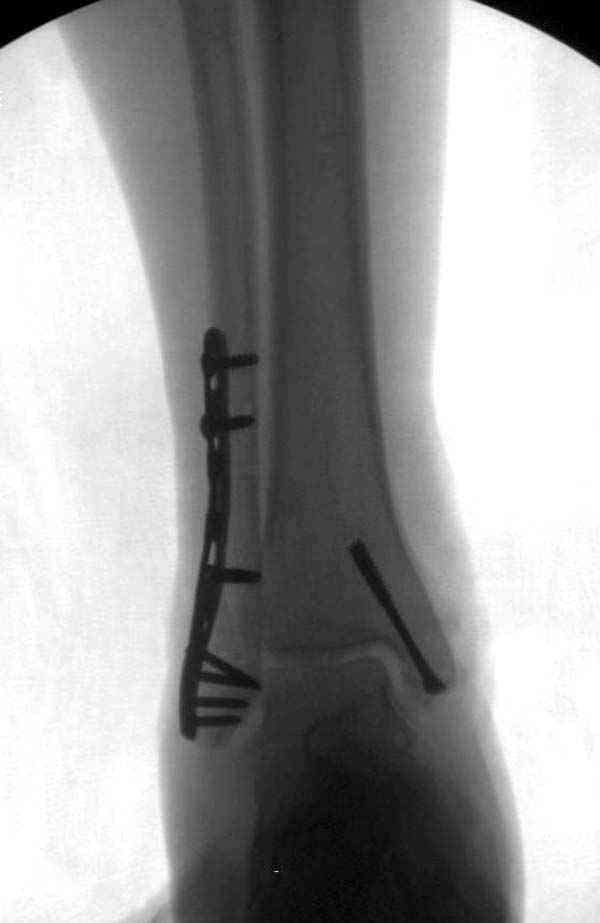

Достаточно быстрое восстановление функции.В октябре 2009г-почувствовала боль,в области рубца над гайкой открылся свищ.На Р-граммах-консолидация переломов и смещение гайки по стяжке.10.11.2009г-конструкции удалены,санация,заживление ран.В настоящее время пациентку ничего не беспокоит.На операции-раскручивание гайки-болталась на конце стяжки.Вопросы:какой механизм раскручивания и что я неправильно сделал?Свои версии:1)в области синдесмоза успела образоваться рубцовая ткань,которая при движении в суставе"пружинила",поскольку голеностопный сустав является спиральным, то и биомеханика подобна кривошипному механизму.2)Реконструктивная пластина не "реконструировалась" по форме лодыжки.Наложил,как есть.То есть подпружинивала сама пластина.Ну,это мои догадки.Что нужно,чтобы избегать впредь таких,пусть и не "страшных"осложнений:Рассверливать через лодыжку область синдесмоза?Ставить шайбу-гровер?Тщательно моделировать пластину?Прилагаю сравнительные снимки-сразу после операции и перед удалением конструкции.

Раз ,есть желание посмотреть другую проекцию выкладываю-ну лучшего качества нет...